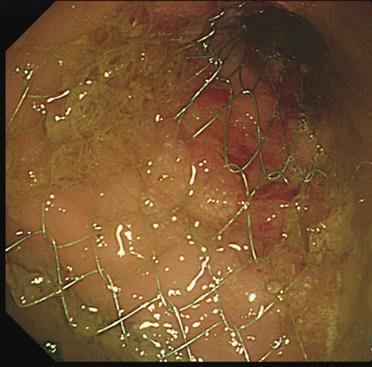

암이 장을 막아 배변이 안 되는 상태일 수 있기 때문이다. 이러한 장폐색은 장에 염증·부종을 야기해 쇼크로 이어질 수 있어 응급조치가 필요하다. 이 경우 인공항문을 만들어 변과 가스를 제거하는 것보다 얇은 금속으로 된 원통 스텐트를 막힌 부위에 넣어 뚫는 방법이 더 효과적으로 사용되고 있다.

대장암 환자 중 장폐색으로 응급 수술을 받아야 하는 경우는 8~13% 정도로 보고되고 있다. 이 경우 스텐트 시술이 널리 사용되고 있다.

곽민섭 교수팀은 스텐트 시술의 안전성과 효과성에 관한 연구를 진행한 결과 응급 수술군과 스텐트 시술군간에 생존률과 재발률에서 차이가 없는 것으로 나타났다.

곽 교수 연구팀은 대장암으로 장폐색이 발생한 환자 113명을 대상으로 연구를 진행했으며, 이 중 42명은 인공항문을 만드는 응급 수술에 들어갔다. 71명은 막힌 장을 뚫는 스텐트 시술을 시행했다.

분석 결과 5년 생존률에 있어 응급 수술군(76.4%), 스텐트군(71.0%)간에 차이가 없었으며, 5년 내 재발률에 있어서도 응급 수술군(71.2%), 스텐트군(66.4%)간에 차이가 없었다.

또 숙련된 전문의에게 시행 시 시술 성공률이 97.6%에 달해 안전성이 확보됐다.

환자들은 인공항문을 만들지 않아 수술 횟수가 3회에서 1회로 감소됐고 1시간 정도 시술 후 장정결로 가스나 변을 제거하면 증상이 완화돼 만족도가 높다.

무엇보다 장의 염증, 부종 등을 처치한 후 수술에 들어갈 수 있어 수술 후 합병증이 감소됐다.

곽 교수는 "이번 연구를 통해 스텐트 시술의 타당성 근거를 마련했다"며 "하지만 스텐트 시술은 장 천공 등 위험 요소를 내포하고 있어 전문 내시경 치료기관을 찾아 숙련된 의사로부터 시술받아야 한다"고 밝혔다.